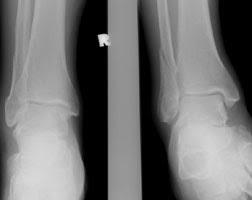

Weber-c-fraktur. Use the information below to gain a better understanding of your injury and what can be done to maximise your recovery. Komplizierte Sprunggelenkfraktur des Fußes mit Syndesmosenbeteiligung Die Einteilung der Frakturen A-C erfolgt nach dem Chirurg Wilhelm Weber 1872-1928. It has a role in determining treatment.

Check Weber-C-Fraktur translations into English. Neben der Weber C Fraktur gibt es auch noch die Fraktur der Klasse A und B.

Weber C Fraktur. Neben der Weber C Fraktur gibt es auch noch die Fraktur der Klasse A und B. Was ist eine Weber-C-Fraktur. DayZ sa well kit DayZ Expansion Building Kits - YouTub. Verschobenem Bruch dislozierte Fraktur undoder. It has a role in determining treatment. Weber C Fraktur. Look up the French to German translation of weber c fraktur in the PONS online dictionary. The Weber ankle fracture classification or Danis-Weber classification is a simple system for classification of lateral malleolar fractures relating to the level of the fracture in relation to the ankle joint specifically the distal tibiofibular syndesmosis.